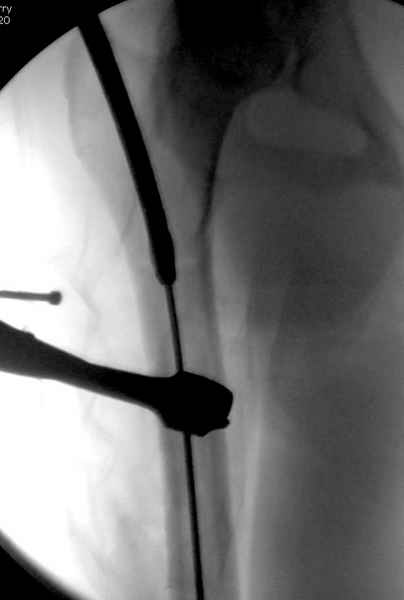

Больной долго оставался нестабильным, только на 14 день удалось заменить на антеградный интромедуллярный штифт TFN (trochanteric femoral nail) SmithNephew. После неудачной попытки закрытой репозиции, несмотря на использование "joystick", проксимальный стержень от

наружного фиксатора, (перелом начал срастаться) репозицию провели из малого доступа, затем остальные этапы операции.

Случай был представлен из-за того, что больного оперировали после наружной фиксации и был риск инфекцирования через места проведения стержней (на снимках), прошло больше 3 месяцев, выписан из амбулаторной службы из-за отсутсвия надобности дальнейшего наблюдения.